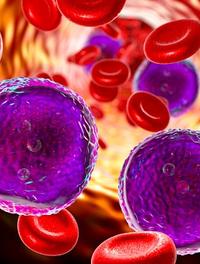

L’incidence de la leucémie aiguë myéloïde (LAM) augmente avec l’âge avec un âge médian au diagnostic d’environ 70 ans. Le pronostic [...]

Les patients de plus de 65 ans atteints de leucémie aigüe myéloïde (LAM) répondent souvent mal à une chimiothérapie d’induction du [...]

Depuis les années 1980, le « 7+3 » (aracytine 7 jours + daunorubicine 3 jours) est le standard du traitement d’induction de la leucémie [...]